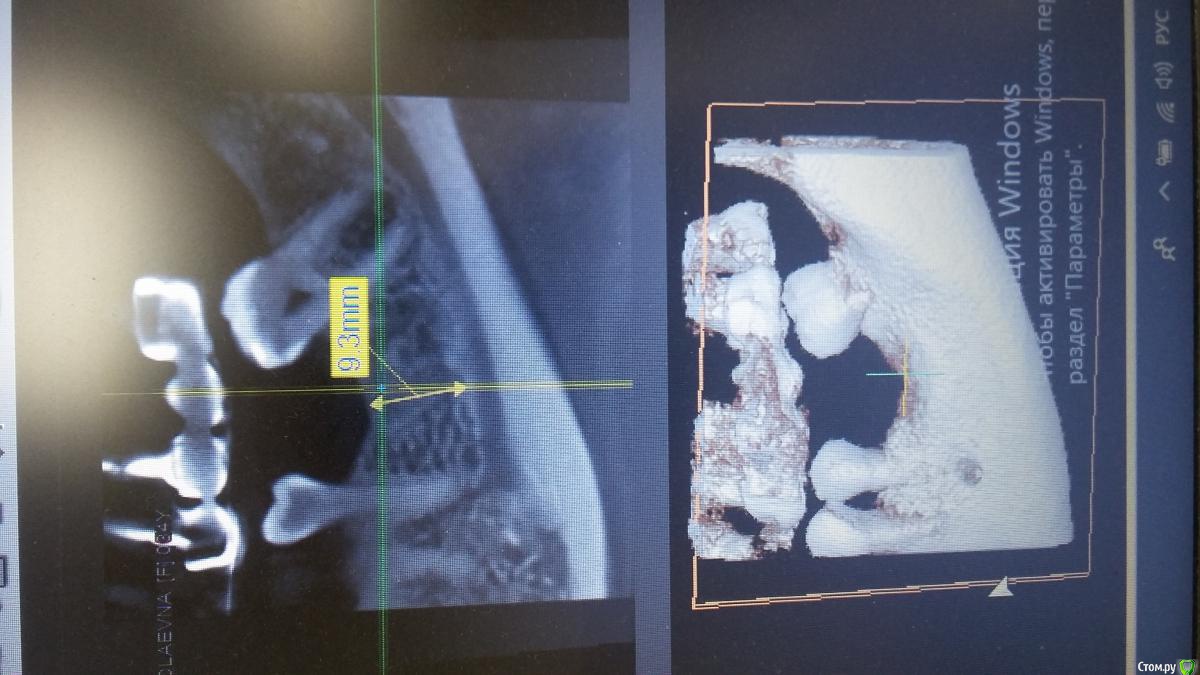

Антон 123 Опубликовано 30 марта, 2019 Поделиться Опубликовано 30 марта, 2019 Добрый день уважаемые форумчане. Посмотрите пожалуйста на скрины. Планируется имплантация 36 . Смущает что удаление было 5 лет назад,а на кт очертания удаленного зуба как будто на прошлой неделе! Ссылка на комментарий

Антон 123 Опубликовано 30 марта, 2019 Автор Поделиться Опубликовано 30 марта, 2019 Вот скрины. Заранее спасибо за мнение опытных товарищей Ссылка на комментарий

Антон 123 Опубликовано 30 марта, 2019 Автор Поделиться Опубликовано 30 марта, 2019 Молодая девушка. Возраст 30 лет. Удаление 36 зуб 5 лет назад. Десна ровная. Жалоб нет. Думаю имплантировать. Кто,что скажет,можно имплантировать? Ссылка на комментарий

Дмитрий М Опубликовано 14 апреля, 2019 Поделиться Опубликовано 14 апреля, 2019 (изменено) Молодая девушка. Возраст 30 лет. Удаление 36 зуб 5 лет назад. Десна ровная. Жалоб нет. Думаю имплантировать. Кто,что скажет,можно имплантировать?возможно фиброзная ткань, если да, то кюретаж и ставить как при одномоментной. отпишитесь по результату Изменено 14 апреля, 2019 пользователем Дмитрий М Ссылка на комментарий